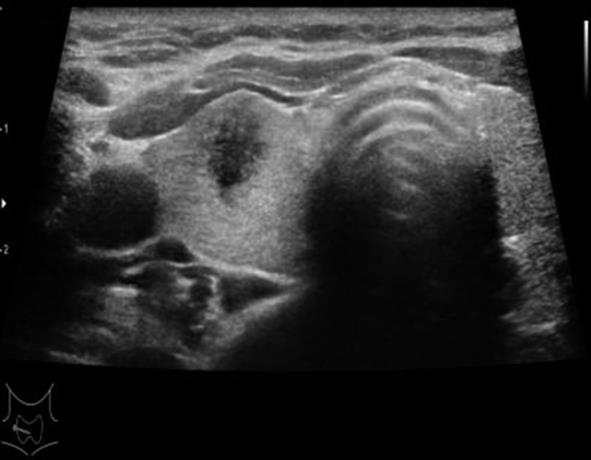

• 基于SEER数据库构建高危PTMC的诊断模型与验证

2023, 48(12):1418-1424. DOI: 10.13406/j.cnki.cyxb.003392

摘要 (71) HTML (47) PDF 1.64 M (177) 评论 (0) 收藏

摘要:目的 探讨高危甲状腺微小乳头状癌(papillary thyroid microcarcinoma,PTMC)的风险预测因子,构建可靠的列线图诊断模型并验证。方法 回顾性分析2004至2015年SEER数据库中手术治疗的PTMC患者(训练集)以及2020至2022年四川省人民医院甲状腺诊疗中心诊治的甲状腺微小结节患者(外部验证集)的临床病理及超声影像资料。验证集中,利用logistic回归分析高危PTMC的风险预测因子,构建列线图诊断模型并采用内部验证集和外部验证集分别进行验证。再根据术前超声影像学特征进行间接评估,探讨术前超声影像学特征预测高危PTMC的可行性与可靠性。结果 训练集纳入患者1 552例,外部验证集纳入患者516例。训练集中筛选出高危PTMC的独立危险因素为性别(男性)、年龄(≤55岁)、结节数目(多灶)、包膜侵犯,颈部淋巴结异常(P<0.05),构建出的列线图C指数为0.946。在训练集及外部验证集中,该列线图模型的预测结果与实际情况均具有较好的一致性。基于超声影像特征诊断高危PTMC的受试者工作特征(receiver operating characteristic,ROC)的曲线下面积(area under the curve,AUC)值为0.931(95%CI=0.910~0.953),与基于病理特征诊断的AUC值具有较高的一致性(κ=0.611,P<0.05)。结论 本研究构建的高危PTMC诊断模型具有较好的预测效应,利用术前超声影像学特征预测高危PTMC具有一定的临床可行性及临床应用价值。